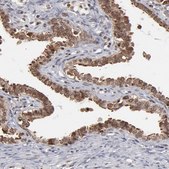

All Prestige Antibodies Powered by Atlas Antibodies are developed and validated by the Human Protein Atlas (HPA) project and as a result, are supported by the most extensive characterization in the industry.

The Human Protein Atlas project can be subdivided into three efforts: Human Tissue Atlas, Cancer Atlas, and Human Cell Atlas. The antibodies that have been generated in support of the Tissue and Cancer Atlas projects have been tested by immunohistochemistry against hundreds of normal and disease tissues and through the recent efforts of the Human Cell Atlas project, many have been characterized by immunofluorescence to map the human proteome not only at the tissue level but now at the subcellular level. These images and the collection of this vast data set can be viewed on the Human Protein Atlas (HPA) site by clicking on the Image Gallery link. We also provide Prestige Antibodies® protocols and other useful information.

• IHC tissue array of 44 normal human tissues and 20 of the most common cancer type tissues.